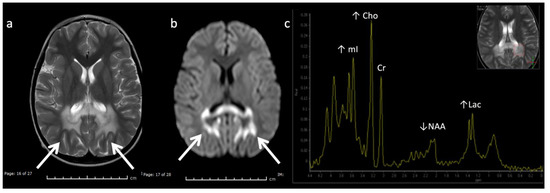

X-linked Adrenoleukodystrophy (ALD) (Figure 12): This peroxisomal disorder is due to a defect in oxidation of long-chain fatty acids resulting in their accumulation. Lesions usually initiate in the callosal splenium and spread into the forceps major, projectional fibers, and auditory and visual pathway; however, in a minority of cases, they may begin in the callosal genu and extend into the forceps minor and beyond [3,41]. Laminated zones of signal alteration in the involved cerebral areas are characteristic, with reduced diffusion and post-contrast enhancement during active demyelination and inflammation, The addition of X-ALD to newborn screen testing has brought about pre-symptomatic MR screening; these scans require careful scrutiny for early/mild changes with special attention to the corpus callosum [42]. Boys with X-ALD should be monitored with serial MRIs based on consensus guidelines [43]. MRS demonstrates decreased NAA and elevated Cho and mI, findings that can improve after successful stem cell transplant [44,45].

Figure 12.

Six-year-old male with X-linked Adrenoleukodystrophy (ALD). (a) Axial T2 and (b) DWI images reveal confluent T2 hyperintensity (a) and reduced diffusion (b) involving the callosal splenium and forceps major/peri-trigonal white matter (white arrows) with sparing of subcortical U-fibers. The pattern of involvement has a postero-anterior and centrifugal pattern. A zonal pattern of signal alteration with mixed diffusion abnormalities indicates acute on chronic demyelination related injury. (c) SV-MRS of the left periatrial white matter reveals decreased NAA (neuronal loss, decreased neuronal-axonal integrity, and/or decreased production), elevated Cho (increased membrane turnover), increased mI (neuroinflammation marker), and increased Lac (anaerobic metabolism).